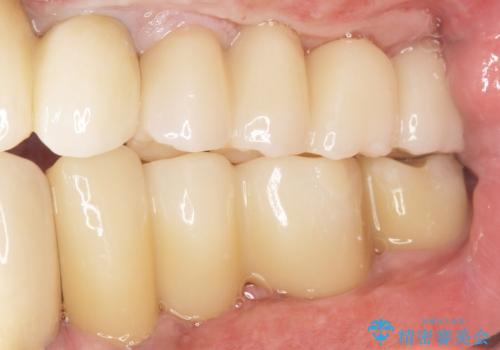

奥歯でしっかりと咬むことができるようになり、喜んで頂けました。

治療終了後には「なんでも食べられるようにしてくれてありがとうございます!」とおっしゃって下さいました。

角化歯肉の移植により、ブラッシング時の歯ぐきの痛みもなくセルフコントロールも良好です。

インプラントの種類:スプラインツイスト(HAコーティング)

固定様式:スクリュー固定

クラウンの種類:ベレッツァクラウン